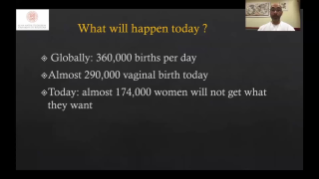

Geli?mi? ZST+ platformu ile desteklenen Nuewa'n?n tam kapsaml? ak?ll? ??zĂŒmleri, ?zellikle gebelik ?ncesi, gebelik ve do?um sonras? iyile?me sĂŒre?lerinde kad?n sa?l???n? iyile?tirmek, seviyeleri giderek daha da artan klinik zorluklar?n ĂŒstesinden gelmek i?in kapsaml? ve verimli tan?lar sunmak ĂŒzere tasarlanm??t?r.